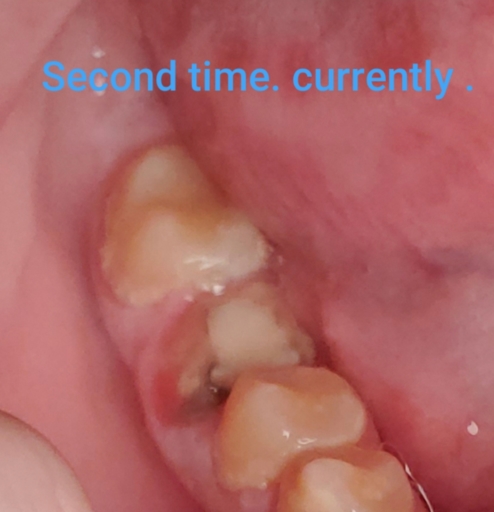

My root canal crown has fell off again after a little over a month . Now it is hurting why is that?

Hi . My crown fell off my root canal . I had the root canal done a little over a month ago . A week later the crown fell off . I went back and they put a new crown on . But now it fell off . The root canal tooth also seems to hurt in a way . Its red...